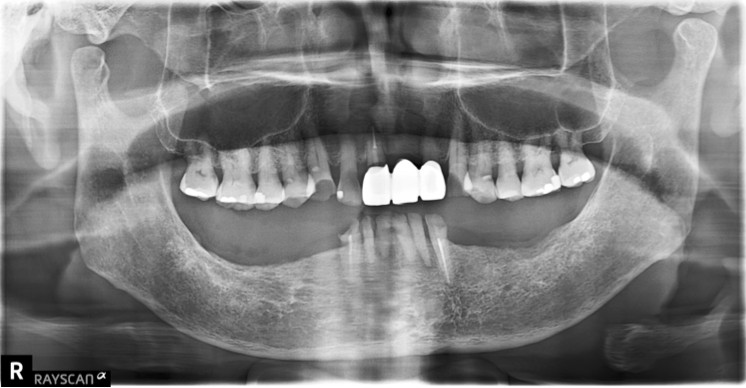

利用活動假牙重建後牙咬合,兼顧美學、預算與實用性的全口重建案例-林先生

【全口重建:下顎無後牙支撐,上顎前牙假牙做了四年以後破損】 【治療醫師:林農翔 醫師】 林先生四年前完成的上顎前牙假牙來診時已經破損,下顎僅剩的六顆牙齒可以說是 …